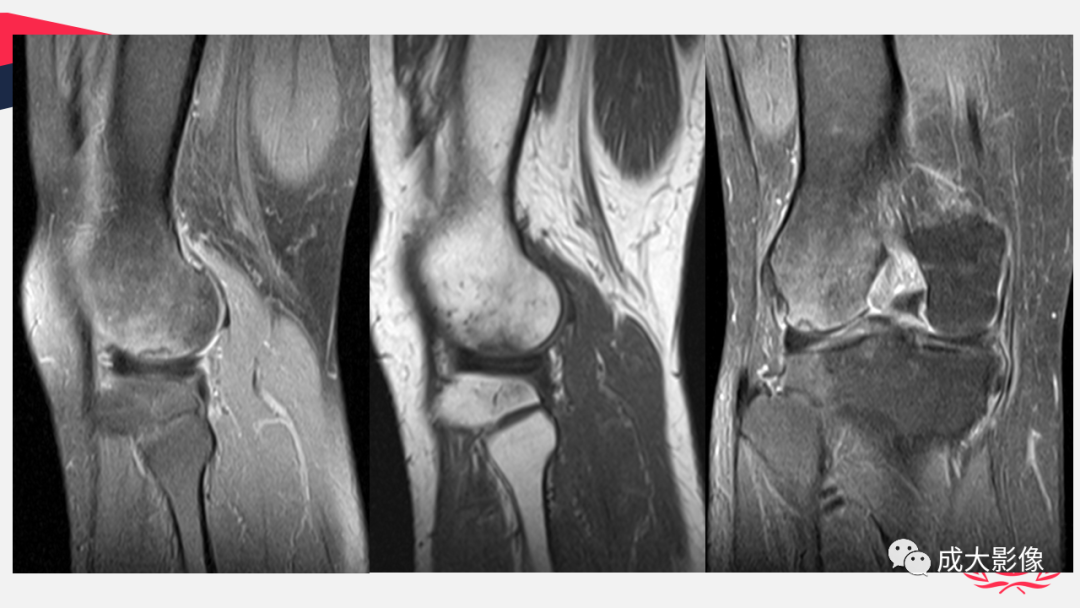

【PPT】剥脱性骨软骨炎-1

【PPT】剥脱性骨软骨炎-2

【PPT】剥脱性骨软骨炎-3